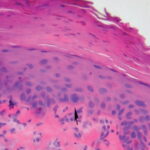

Actinic keratoses are keratinocytic dysplasias or squamous cell carcinomas in situ. This definition is preferable to their designation as precancerous because most of them never progress to cancers. Biologically, the lesions are still benign; invasion into the dermis, if present at all, is limited to the most superficial portion, the papillary dermis (see Differential Diagnosis) . |

This variety of keratosis, sometimes referred to as florid keratosis, may easily be overdiagnosed as invasive squamous cell carcinoma by the unwary. Mild or moderate papillomatosis may be present. The epidermis is thickened in most areas and shows irregular downward proliferation that is limited to the uppermost dermis and does not represent frank invasion .A varying proportion of the keratinocytes in the stratum malpighii show a loss of polarity and thus a disorderly arrangement. Some of these cells show pleomorphism and atypicality (“anaplasia”) of their nuclei, which appear large, irregular, and hyperchromatic. Often the nuclei in the basal layer are closely crowded together. Some of the cells in the midportion of the epidermis show premature keratinization, resulting in dyskeratotic cells or apoptotic bodies characterized by homogeneous, eosinophilic cytoplasm with or without a nucleus. In contrast to the epidermal keratinocytes, the cells of the hair follicles and eccrine ducts that penetrate the epidermis within actinic keratoses retain their normal appearance and keratinize normally. Occasionally, cells of the normal adnexal epithelium extend over the atypical cells of the epidermis in an umbrella-like fashion. In some cases, abnormal keratinocytes extend downward on the outside of the follicular infundibulum to the level of the sebaceous duct and, less commonly, along the eccrine duct . |

A variant of the hypertrophic type of actinic keratosis is the lichenoid actinic keratosis, which demonstrates nuclear atypia, irregular acanthosis and hyperkeratosis, the presence of basal cell liquefaction, degeneration of the basal cell layer, and a bandlike “lichenoid” infiltrate in close apposition to the epidermis . Fairly numerous eosinophilic, homogeneous apoptotic bodies are seen in the upper dermis as so-called Civatte bodies. Aside from the presence of nuclear atypicality, |